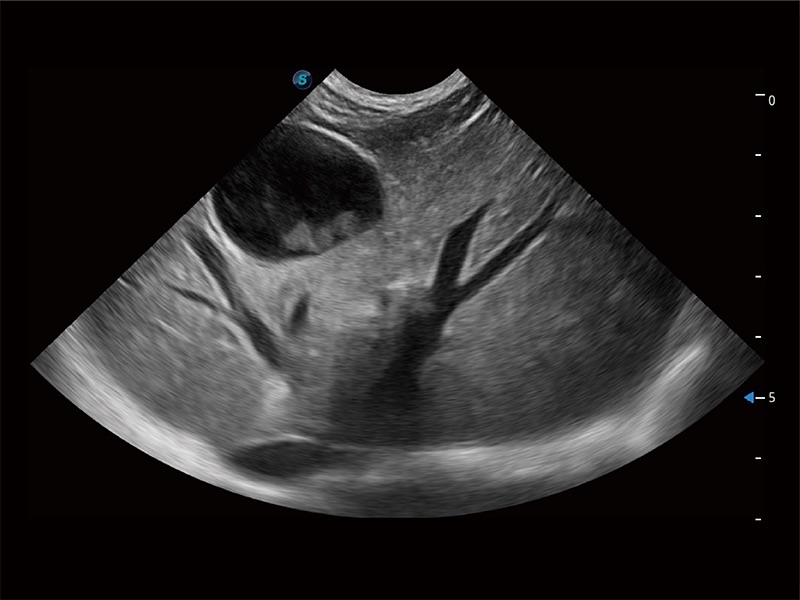

高性能和先进的临床应用工具可以为动物医生提供临床信心。ProPet 80 搭载了先进的腹部和浅表应用工具,帮助医生在日常临床实践中发挥前所未有的作用。

ProPet 80 专为动物医生设计,对不同的动物体型和生理结构作出了针对性的优化。通过动物影像专用软件,可满足个性化的应用需求,帮助动物医生获得更精确的诊断数据。

ProPet 80 全新的动物超声智能软件和丰富的探头群,为动物医生提供了高清晰度和精细分辨率的图像,无论在宠物、马科、畜牧还是实验室动物等应用中都可以轻松应对,为您的日常工作带来满意的体验。